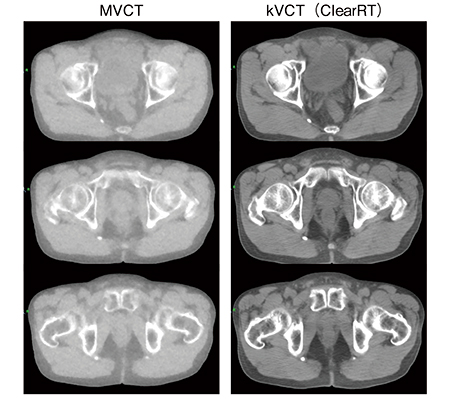

図5 従来のMVCTとkVCT(ClearRT)との画質の違い

軟部組織の分解能が向上し,診断用CTにより近い画質となった。